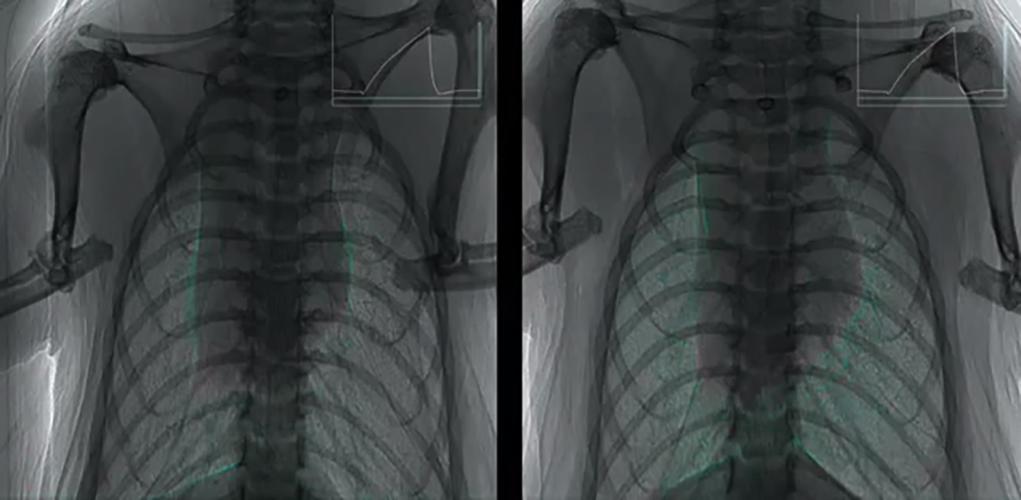

We have previously established a method for examining and quantifying regional lung function deficits in vivo. The process, known as 4DXV combines four-dimensional computed tomography using phase-contrast x-ray imaging with x-ray velocimetry enables us to make local measurements of airflow through the airway tree and regional lung lobes. The image below shows the results from β-ENaC mice, a well-established mode of cystic fibrosis-like disease, and their healthy littermates. We have shown that it is possible to identify the location of lung disease.

In 2016 he and collaborators from Monash University published the first demonstration of the use of X-ray Velocimetry (XV), an X-ray based pulmonary function testing for the quantification of lung disease heterogeneity in B-ENaC mice. This unique and world-leading imaging method gathers lung motion information during normal breathing, and has revolutionary potential since it can detect, quantify and follow changes in regional lung function over time. He now has industry collaborations with 4DMedical (Prof Andreas Fouras) who have commercialised this technology. This work has been funded by the NHMRC, MRFF and other funding bodies.